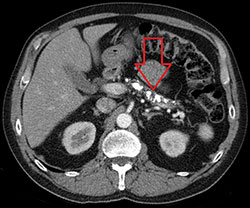

• ภาพถ่ายรังสี (CT, MRI, MRCP): พบการหดตัวของตับอ่อน แคลเซียมเกาะในตับอ่อน หรือท่อน้ำตับอ่อนตีบและขยายสลับกัน